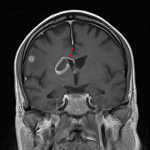

MRI

- Multifocal areas of parenchymal restricted diffusion involving the bilateral cerebral and cerebellar hemispheres

- The largest lesion is located in the anterior right basal ganglia/anterior limb of the right internal capsule, which measures 3 x 2.5 x 2.3 cm, demonstrates peripheral enhancement which is incomplete along its ependymal margin, and demonstrates central restricted diffusion

- Linear enhancement extends along the superior margin of the right lateral ventricle

- Surrounding vasogenic edema, particularly involving the right basal ganglia and right frontal subcortical lesions

- No substantial midline shift or evidence of herniation or hydrocephalus